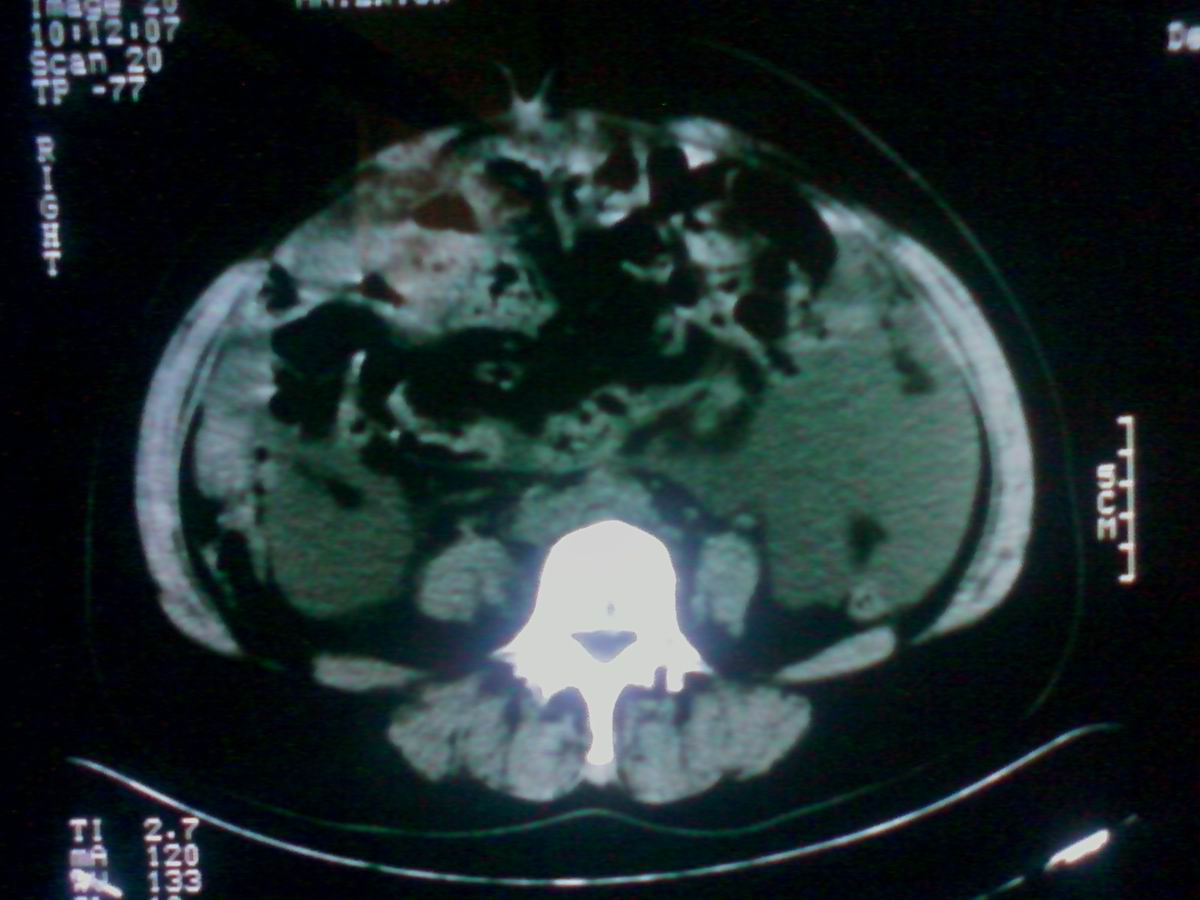

标题: CT25799:女性患者,45岁,腹胀,上腹部疼痛来诊,B超示盆腔 [打印本页]

标题: CT25799:女性患者,45岁,腹胀,上腹部疼痛来诊,B超示盆腔

考虑卵巢癌伴腹水

1)考虑卵巢恶性肿瘤。2)腹水。